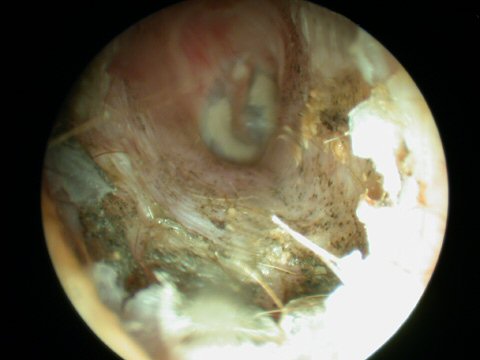

Fungal infection of the ear canal